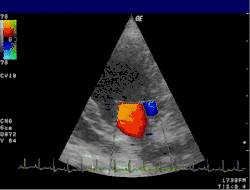

Doppler echocardiography is a procedure that uses Doppler ultrasonography to examine the heart.[1] An echocardiogram uses high frequency sound waves to create an image of the heart while the use of Doppler technology allows determination of the speed and direction of blood flow by utilizing the Doppler effect.